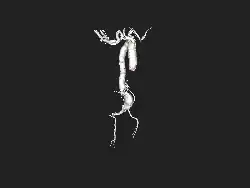

An aneurysm is an outward bulging, likened to a bubble or balloon, caused by a localized, abnormal, weak spot on a blood vessel wall.[1] Aneurysms may be a result of a hereditary condition or an acquired disease. Aneurysms can also be a nidus (starting point) for clot formation (thrombosis) and embolization. As an aneurysm increases in size, the risk of rupture increases, which could lead to uncontrolled bleeding.[2] Although they may occur in any blood vessel, particularly lethal examples include aneurysms of the circle of Willis in the brain, aortic aneurysms affecting the thoracic aorta, and abdominal aortic aneurysms. Aneurysms can arise in the heart itself following a heart attack, including both ventricular and atrial septal aneurysms. There are congenital atrial septal aneurysms, a rare heart defect.

Fusiform aneurysms ("spindle-shaped" aneurysms) are variable in both their diameter and length; their diameters can extend up to 20 cm (7.9 in). They often involve large portions of the ascending and transverse aortic arch, the abdominal aorta, or, less frequently, the iliac arteries.[3]: 357

- The aorta, namely aortic aneurysms including thoracic aortic aneurysms and abdominal aortic aneurysms.[9]